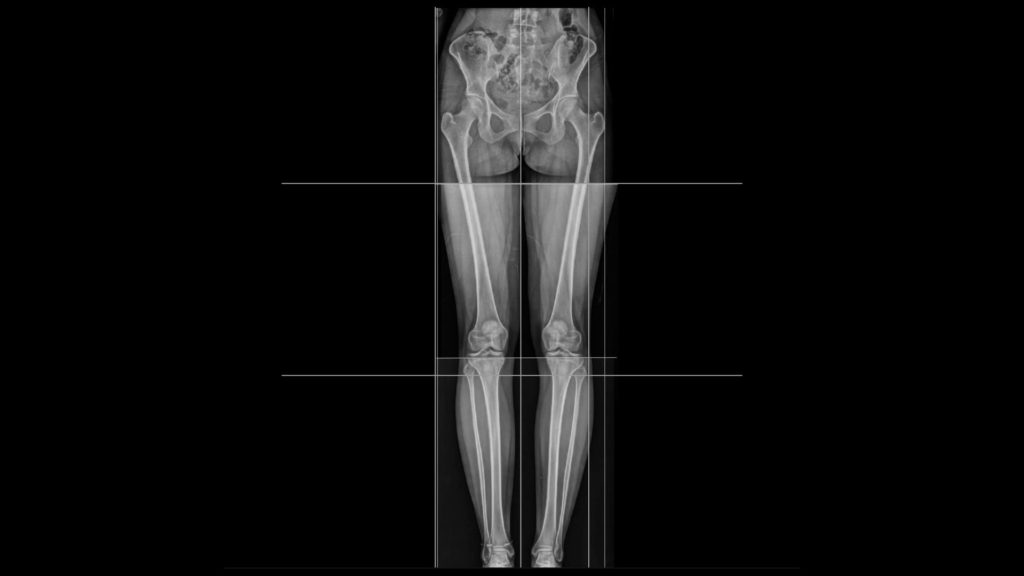

Telerradiografía o radiografías panorámicas

Son radiografías especiales tomadas a mayor distancia del individuo en donde se podrá apreciar varios segmentos a la vez:

Miembros inferiores (pelvis-fémur -tibia/peroné- tobillos).